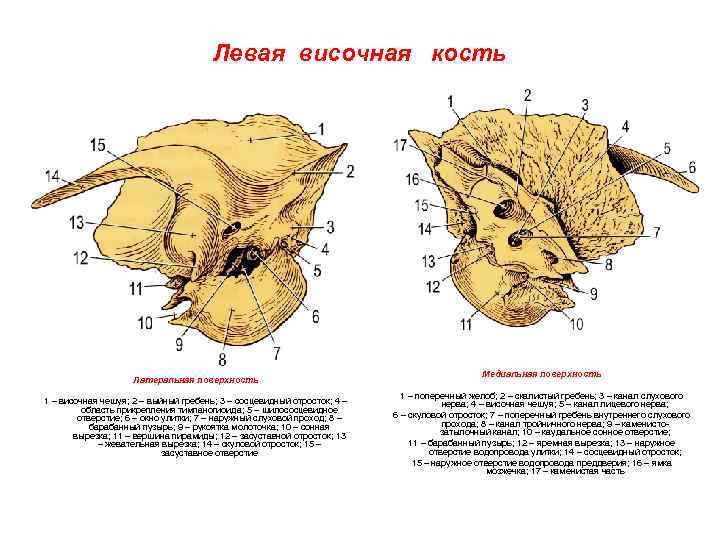

Анатомия сосцевидного отростка